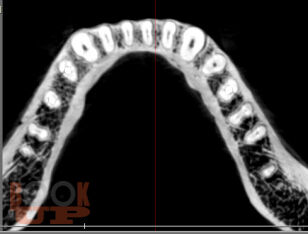

Учебное пособие предназначено для студентов стоматологического факультета, врачей-ординаторов и стоматологов практического здравоохранения. Содержит информацию о внедрении компьютерных программ в эндодонтии, которые позволяют моделировать клинические ситуации в рамках виртуального пространства, что дает возможность заблаговременно предотвращать ошибки и осложнения, оценивать эффективность лечения, прогнозировать отдаленные результаты.